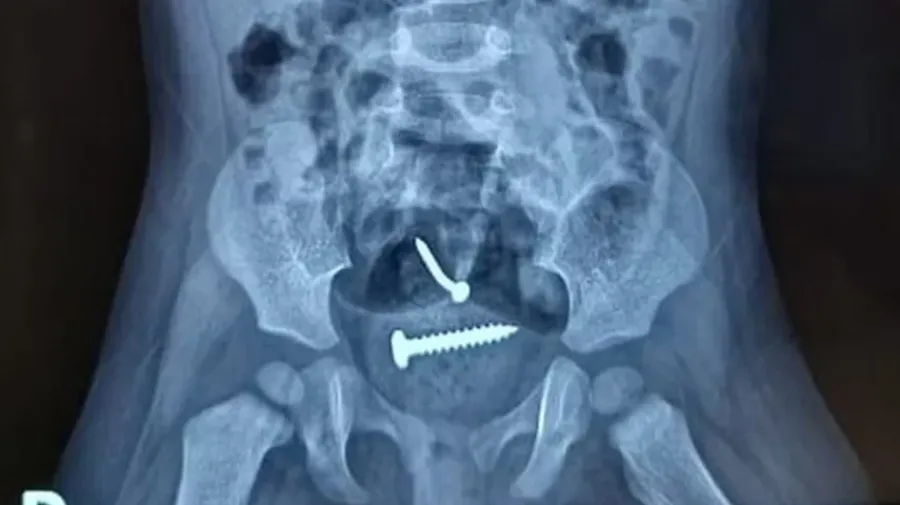

O laudo médico da bebê de 1 ano, que estava com um prego e parafuso dentro do corpo, revela que não houve violência sexual. O suspeito de ter agredido mãe e filha prestou depoimento na delegacia da cidade de Pedro II e negou ter abusado da bebê.

A sua companheira também negou, que o pai tenha cometido algo contra a criança. O laudo também mostrou que a criança engoliu os objetos e que os mesmos foram expelidos de forma natural, não precisando de intervenção cirúrgica.